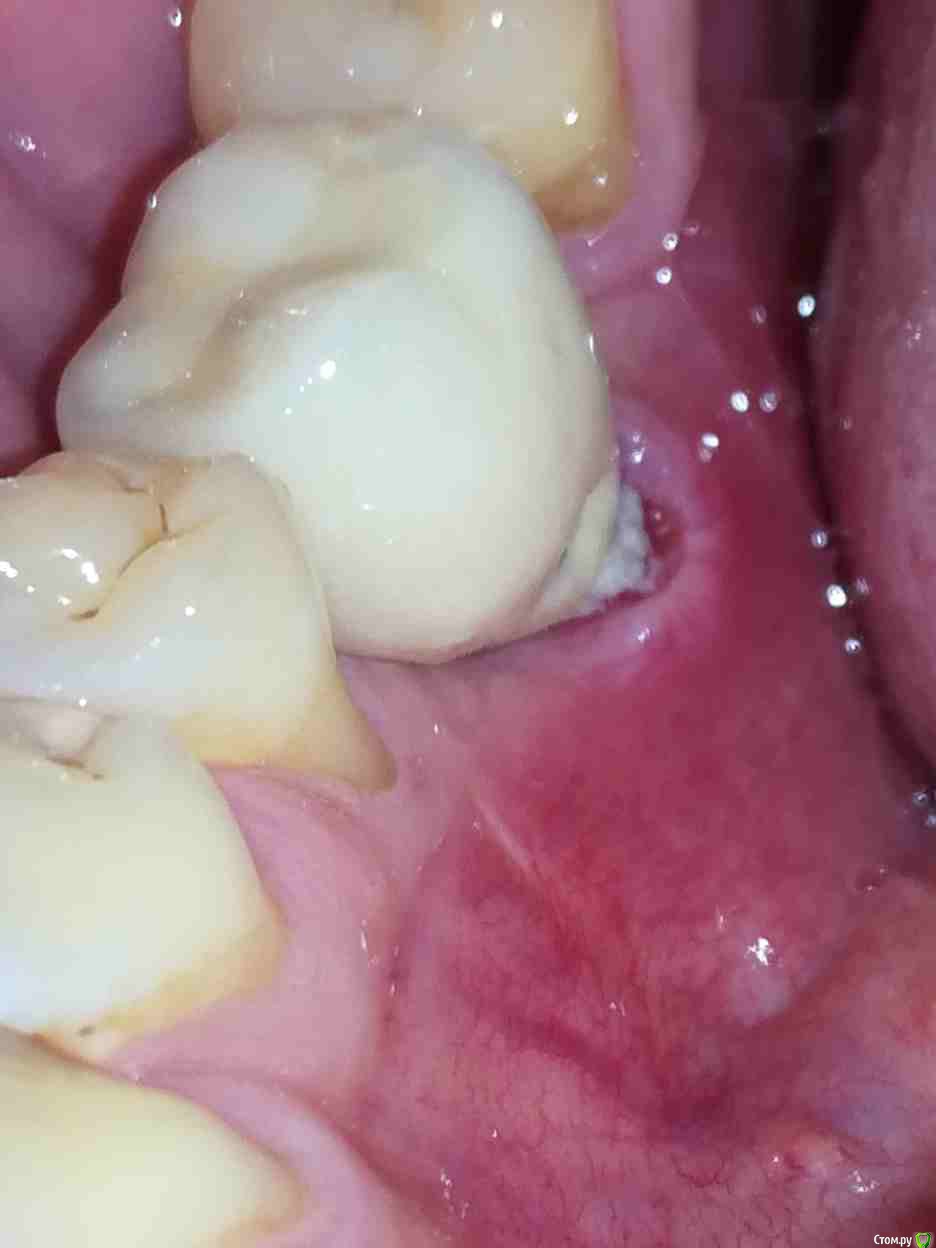

Alex19_73 Опубликовано 15 февраля, 2017 Поделиться Опубликовано 15 февраля, 2017 Доброго времени суток!Оцените пожалуйста качество имплантации и последующего протезирования. Имплантация проводилась с расщеплением гребня, имплант оказался смещен внутрь относительно других зубов. Хотел металлокерамическую коронку на винте, но ортопед сказал что возможно поставить только на цементе т.к. имплант сильно смещён внутрь. Вчера установили коронку но после дома стал разглядывать и она мне совсем не понравилась. По ощущениям очень неприятна, громоздка, когда жуешь то же как то не как родной зуб, языки щека постоянно по ней трут. С обратной стороны коронки обнаружил что то белое, наверно цемент, зубочисткой и ирригатором снять не удалось. Ортопед обратную поверхность зуба ковырял крюком счищая цемент. Это белое спускается с коронки прямо на десну.Можно ли если это цемент счистить его не испортив керамику коронки? Не может ли спровоцировать переимплантит такое затекание цемента, и вообще насколько это профессионально и соответствует протоколам (работа имплантолога и ортопеда)? Заранее спасибо. Ссылка на комментарий

Alex19_73 Опубликовано 16 февраля, 2017 Автор Поделиться Опубликовано 16 февраля, 2017 Как оказалось позже, во время еды, под зуб ещё и большие куски еды попадают и там остаются, флос под зубом проходит очень свободно. Ссылка на комментарий

Alex19_73 Опубликовано 3 апреля, 2017 Автор Поделиться Опубликовано 3 апреля, 2017 Первую пластику десны сделали, фото ниже, на днях намечена вторая операция пластики десны.Но обнаружилась проблема в том месте в котором подозревал ее изначально. В четверг начал разглядывать десну со стороны языка и показалось подозрительным что ее край слишком светлый. Разглядел что в районе края десны на коронке какая то неоднородность, ощущение что она трет по десне и похоже десна уже несколько опустилась и вдобавок там не заживающая рана. Фото с кровью было сделано утром до чистки зубов, хотел сделать фотографию, но мешали пузырьки слюны, провел по десне языком и пошла кровь.Врачу еще об этом не говорил. Помогите пожалуйста определиться с тем что делать в такой ситуации, что просить у врача, что должен сделать врач. Коронка несъемная. Ее можно только распилить. Ссылка на комментарий